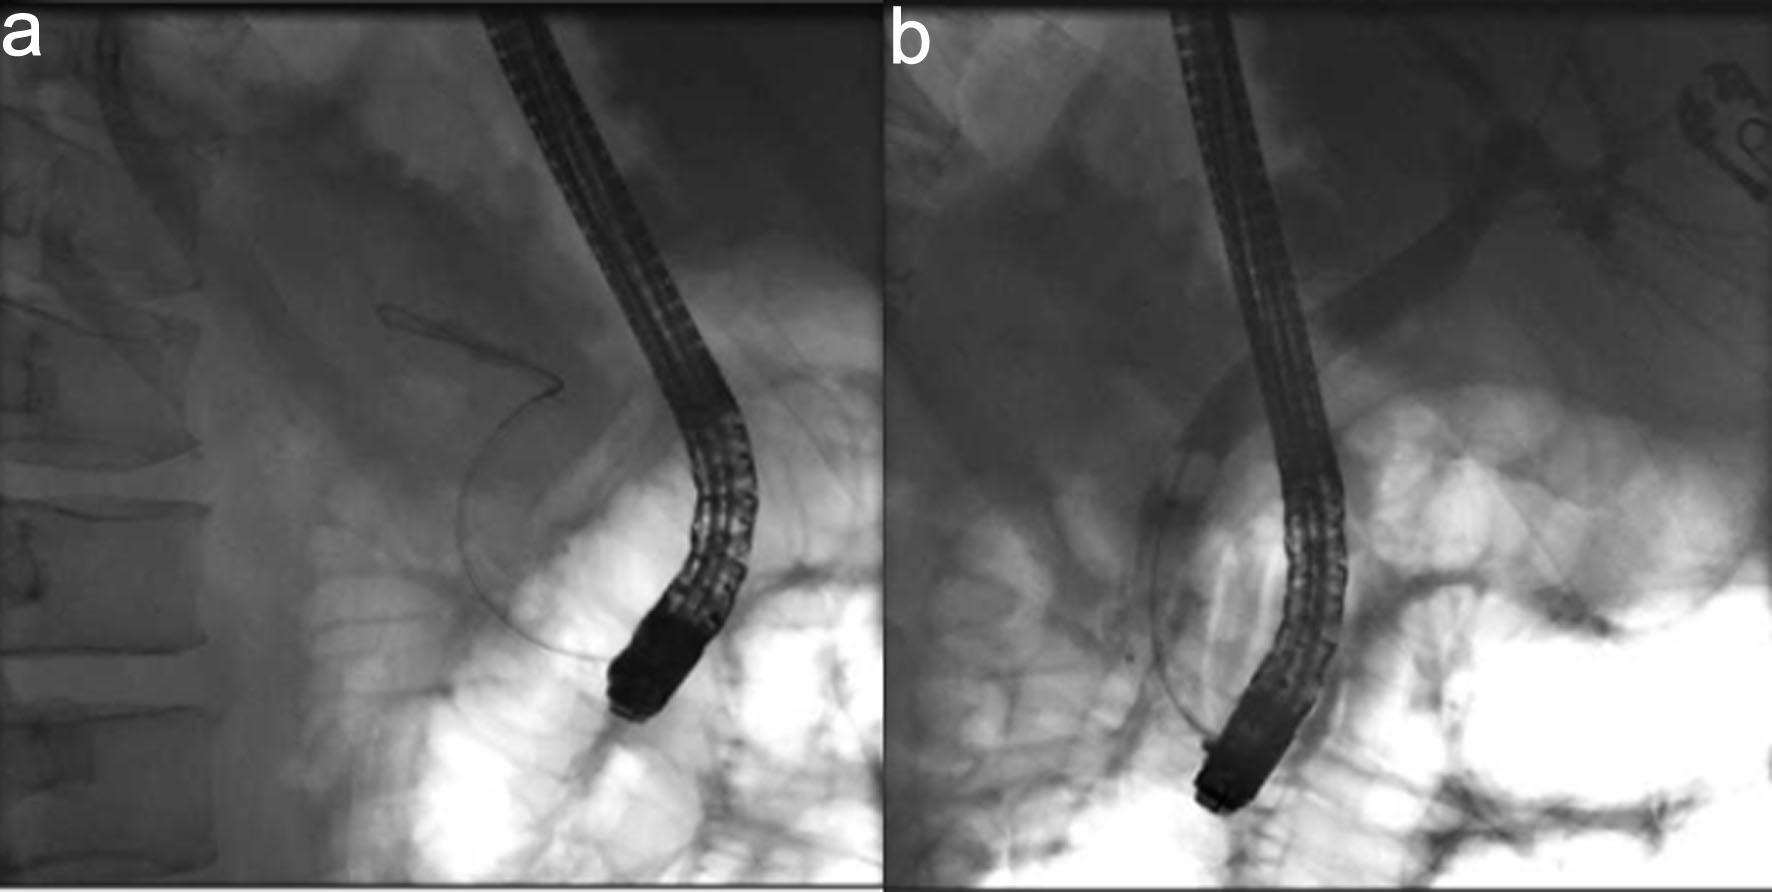

An emergent ERCP was performed. The major papilla appeared small, and the pancreatic duct was normal. The cholangiogram demonstrated a dilated biliary tree with multiple filling defects (Fig. 3a, b). A biliary sphincterotomy was performed, and the bile ducts were swept, yielding blood clots that were subsequently removed. A prophylactic pancreatic duct stent was placed to prevent post-ERCP pancreatitis. A temporary plastic stent was placed in the common bile duct to facilitate drainage (Fig. 4a, b).

Figure 3. Cholangiogram. (a) Fluroscopic image revealing wire cannulation of bile duct. (b) Cholangiogram revealing a dilated biliary tree with filing defects.